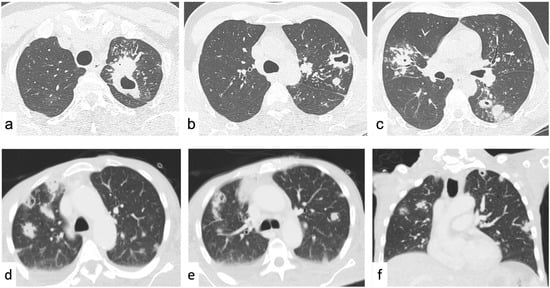

4.2.3. Increased Lung Attenuation

Ground-Glass Opacities

Consolidations

- Miller, W.T.; Shah, R.M. Isolated Diffuse Ground-Glass Opacity in Thoracic CT: Causes and Clinical Presentations. Am. J. Roentgenol. 2005, 184, 613–622. [Google Scholar] [CrossRef]

- Park, C.M.; Goo, J.M.; Lee, H.J.; Lee, C.H.; Chun, E.J.; Im, J.-G. Nodular Ground-Glass Opacity at Thin-Section CT: Histologic Correlation and Evaluation of Change at Follow-Up. RadioGraphics 2007, 27, 391–408. [Google Scholar] [CrossRef]

- Parekh, M.; Donuru, A.; Balasubramanya, R.; Kapur, S. Review of the Chest CT Differential Diagnosis of Ground-Glass Opacities in the COVID Era. Radiology 2020, 297, E289–E302. [Google Scholar] [CrossRef] [PubMed]